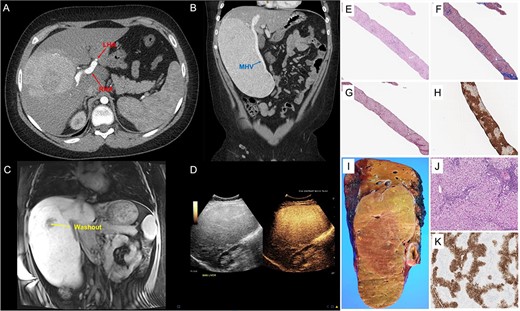

A 14-year-old boy presented with abdominal pain. Abdominal ultrasonography and CT scan revealed a liver mass 21 cm in greatest dimension (Fig. 1A–D). The right hepatic artery (RHA) supplying the mass was enlarged, while the left hepatic artery (LHA) was small in caliber (Fig. 1A). The middle hepatic vein (MHV) was enlarged (Fig. 1B), and a diminutive left hepatic vein suggested vascular steal. He had elevated transaminases; alanine aminotransferase (ALT) = 129 (normal 0–40), aspartate aminotransferase (AST) = 60 (normal 0–40). Serum alpha fetoprotein (AFP) was normal; AFP = 2 (normal 0.8–12). MRI of the liver with hepatocyte-specific contrast (gadoxetate disodium) revealed a 14 × 11 × 21 cm, PRETEXT II lesion involving segments V, VI, VII and VIII [8]. Most of the mass retained contrast in the 20-minute hepatocyte phase except a small, central area that washed out (Fig. 1C). The MRI revealed underlying steatosis in the left liver and fat-containing nodules throughout the mass. Contrast-enhanced ultrasound revealed homogenous hyperenhancement (Fig. 1D) in the early arterial phase that was retained through delayed imaging. Because the etiology of the mass and the underlying liver disease remained unclear, ultrasound-guided percutaneous biopsy of the lesion and the adjacent non-neoplastic liver was performed.

GFNH; (A–D) representative images from CT of the abdomen and pelvis with contrast, MRI of the liver with gadoxetate disodium and contrast-enhanced ultrasound; (A) the large, heterogenous mass in the right liver with an enlarged RHA and a diminutive LHA, and panel (B) further characterizes its exophytic nature, also demonstrating the enlarged MHV; panel (C) depicts a coronal section of an MRI of the liver with gadoxetate disodium showing the 14 cm × 11 cm × 21 cm, PRETEXT II lesion involving segments V, VI, VII and VIII and a small, central area of washout, and panel (D) shows homogenous hyperenhancement of the liver lesion on contrast-enhanced ultrasound; (E–K) pathological features of giant focal nodular hyperplasia; (E–H) needle core biopsy; proliferation of well-differentiated hepatocytes displaying a nodular architecture (E, Hematoxylin & Eosin, 40×) and separated by bands of fibrosis (F, trichrome stain, 40x and G, reticulin stain, 40×), and GS immunostain shows a geographic pattern (H, immunohistochemistry, 40×); (I and J) partial hepatectomy (segments 5, 6, 7 and 8) with cholecystectomy; coronal section of the right hepatectomy specimen demonstrating a tan-yellow and well-circumscribed mass measuring 22.1 × 13.0 × 6.0 cm (I, gross picture) with hepatocellular proliferation with nodular architecture and containing occasional abnormal vessels and ductules (J, Hematoxylin and Eosine, 100×); GS performed in the resection specimen also displays a geographic pattern of staining (K, immunohistochemistry, 40×).

Histologically, the non-neoplastic liver revealed moderate microvesicular and macrovesicular steatosis with mild inflammatory infiltrate. No significant fibrosis was noted. H&E-staining of the liver mass demonstrated proliferation of well-differentiated hepatocytes displaying nodular architecture separated by bands of fibrosis highlighted by trichrome staining. Endothelialization of sinusoids was observed with an incomplete pattern of CD34 staining. Reticulin staining emphasized that most cell plates were no more than 2–3 hepatocytes in thickness. Bile duct proliferation was noted at the periphery of the nodules, best appreciated with the aid of cytokeratin 7. Glutamine synthetase (GS) staining showed a geographic pattern with hepatocyte sparing close to the fibrous band (Fig. 1E–H). Glypican-3 and Sall4 immunostains were both negative. Beta-catenin staining showed only membranous/cytoplasmic reactivity. No aberrant nuclear accumulation of beta-catenin was observed. Based on these findings, the differential diagnosis included several well-differentiated hepatocellular lesions, including FNH, hepatic adenoma, well-differentiated hepatocellular carcinoma (HCC) and fibrolamellar HCC.

The geographic pattern of GS staining coupled with the imaging findings pointed to a probable diagnosis of FNH, although well-differentiated HCC and hepatic adenoma could not be entirely excluded. The etiology of the steatosis in this patient was unclear, but it may be associated with his increased body mass index (31.3 kg/m2). Given the patient’s symptoms and the possibility of malignancy, we proceeded with right hepatectomy. The patient was discharged home on post-operative Day 9 due to rehabilitation requirements, an episode of opiate-induced delirium and a surgical wound complication (seroma). Post-operative follow-up demonstrated a normalization of the patient’s AST and ALT. After unremarkable MRIs at 3 and 6 months, the patient was discharged from clinic.

Gross examination of the right hepatectomy specimen (1927 g, 24.0 × 16.5 × 6.0 cm) revealed a well-circumscribed nodular lesion (22.1 × 13.0 × 6.0 cm; Fig. 1I and J). Immunostaining for GS was performed, revealing the same map-like staining pattern observed in the biopsy (Fig. 1K). The large fibrous septae were highlighted with trichrome stain. The overall findings were consistent with FNH. Additional stains performed with negative results included liver fatty acid-binding protein (LFABP), hepatic amyloid A and c-reactive protein (CRP), ruling out the possibility of HA or malignancy.